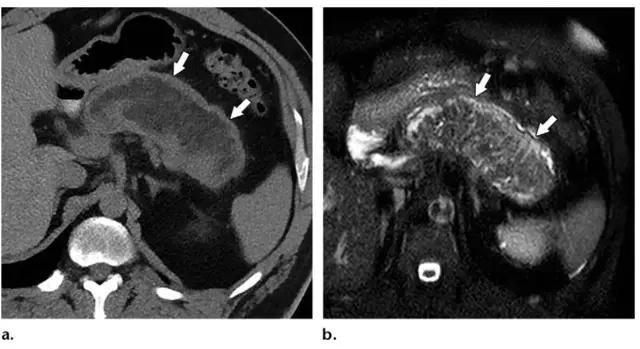

同时受累的亚型:表现为胰腺及胰周无强化坏死物,多累及小网膜囊和肾前间隙(图 3a)。

胰周型:表现为胰腺强化正常,而胰周坏死,坏死物可包括不等量的液体和和非液性成分,约占坏死性胰腺炎的 20%(图 3b)。

图 3 坏死性胰腺炎亚型在增强轴位 CT 的表现。a 胰腺和胰周同时受累的 58 岁女性患者,胰体无强化(*),正常强化的胰尾(黑箭头),小网膜囊内 ANC(白箭头)。b 仅胰周受累的 18 岁男性患者,可见一周为大片不均质密度(箭头),和 ANC 相符。胰腺实质密度正常(*)。c 仅胰腺实质受累的 33 岁男性患者,可见大片局限无强化的胰腺实质和脂肪密度(*),诊断为 WON。仅周边可见少量残余强化的胰腺实质(箭头)